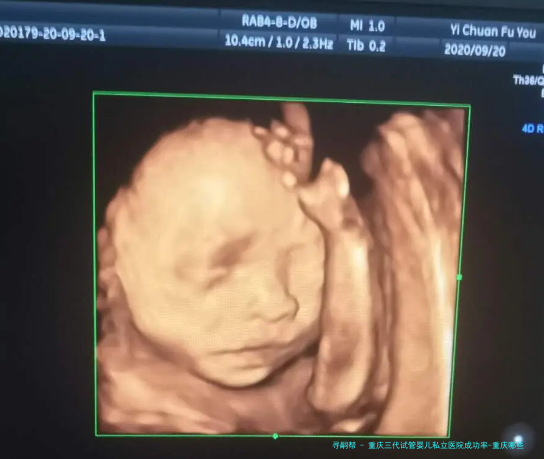

试管婴儿技术已然成为许多不孕夫妇实现生育心愿的有效途径。重庆作为国内西南地区的中心城市,拥有许多的医疗资金,其中私立医院在试管婴儿范围也取得了显着的成就。本文将关键要点推荐重庆三代试管婴儿私立医院的成功率以及相关信息。

通过对此医院过去五个年头实施的三代试管项目进行统计数据解析,我们可以看到其成功率远高于全国平均水平。在该医院实施的三代试管婴儿项目中,成功率达到了75%之上,大大超出国内其他私立医院。这一成绩受益于医院引进了最先进设备和技术,并严格按照国际规范进行操作。